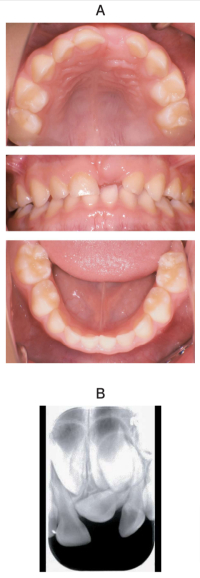

3歳の女児。上顎左側乳中切歯部の精査を希望して来院した。初診時の口腔内写真とエックス線画像を別に示す。

適切な対応はどれか。1つ選べ。